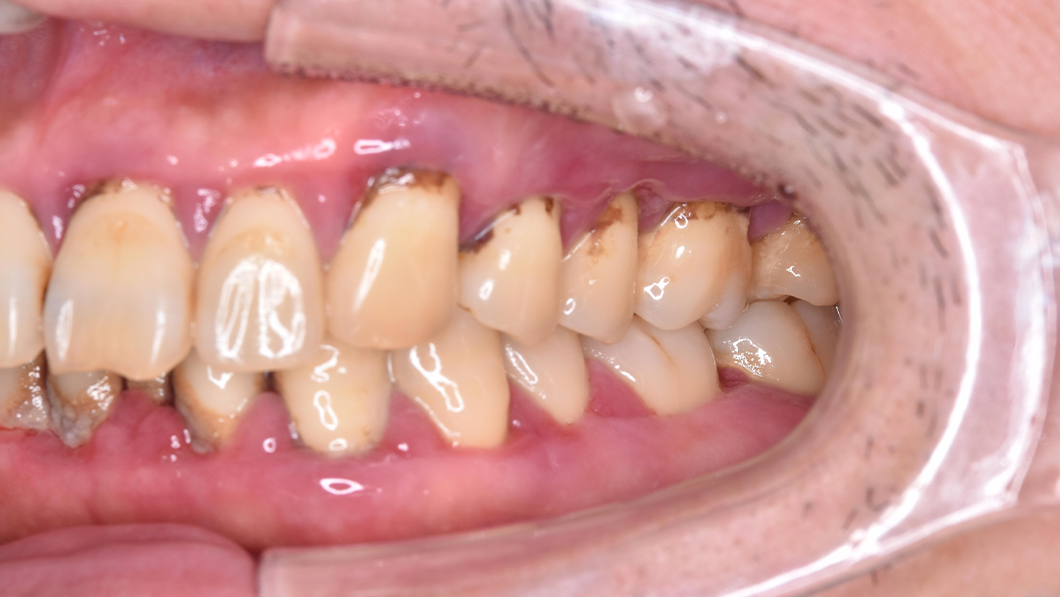

【40代 男性】歯周基本治療

治療前

主訴 全額的歯周病による歯周組織の炎症

治療内容 SC、SRP、歯科衛生士実地指導、TCH指導